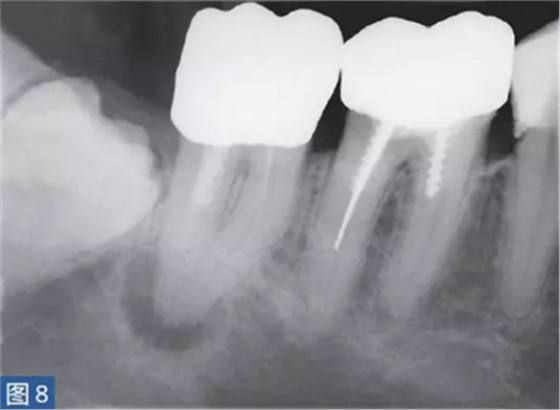

急性根尖周膿腫(AAA acute apical abscess)

急性根尖膿腫(圖8 和9)是一種局部的或者彌漫性的液性病變。由壞死牙髓產(chǎn)生的微生物和非微生物刺激所引起的嚴(yán)重炎癥反應(yīng)造成了根尖周組織的破壞。患者通常表現(xiàn)出中度至重度疼痛,根據(jù)嚴(yán)重程度還可能出現(xiàn)發(fā)熱和白細(xì)胞增多的全身癥狀。

臨床診斷顯示牙髓電活力測(cè)試結(jié)果陰性。叩診和觸診通常會(huì)引起疼痛。如果膿腫僅限于骨內(nèi),則不出現(xiàn)腫脹癥狀。放射學(xué)檢查,根尖周組織表現(xiàn)從無變化到發(fā)生明顯變化。

圖8:47 牙齒AAA。術(shù)前X 線片?;颊呔驮\時(shí)有發(fā)燒癥狀,且叩診和觸診疼痛明顯。